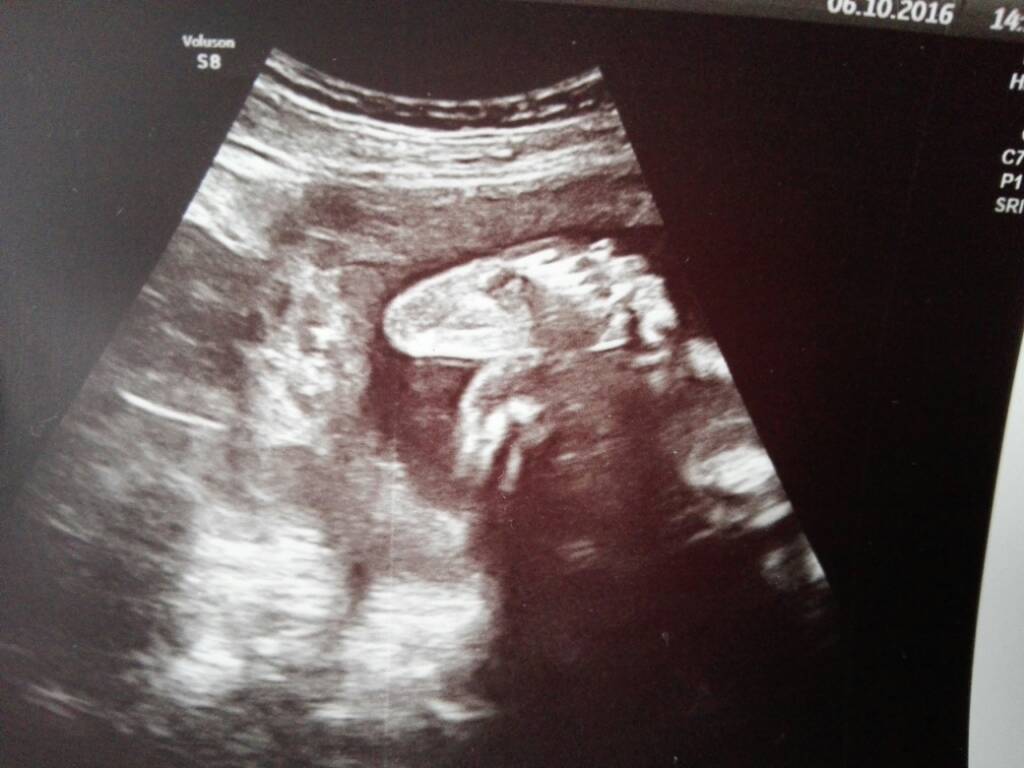

Witam po wizycie. Wszystko ok, dzidziuś trochę duży jak na 26 tydzień,ale nie mam się martwić. Wazy około 1 kg,główka chwilowo w dole, nisko. Na przyszły tydzień picie glukozy [emoji13]

A oto stópka co mnie kopie [emoji7] Zobacz załącznik 776856